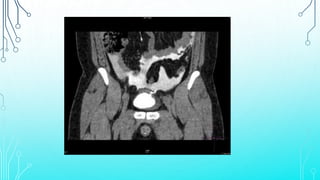

•CT cystography is an excellent method for detecting

bladder rupture; however, retrograde filling of the

bladder with 300 mL of contrast medium is

necessary to distend the bladder completely.

• Incomplete distention with consequent missed

diagnosis of bladder rupture often occurs when the

urethral catheter is clamped during standard

abdominal CT scan with intravenous contrast

injection.

•CT cystography isan excellent method for detecting bladder rupture; however, retrograde filling of the bladder with 300 mL of contrast medium is necessary to distend the bladder completely. • Incomplete distention with consequent missed diagnosis of bladder rupture often occurs when the urethral catheter is clamped during standard abdominal CT scan with intravenous contrast injection.